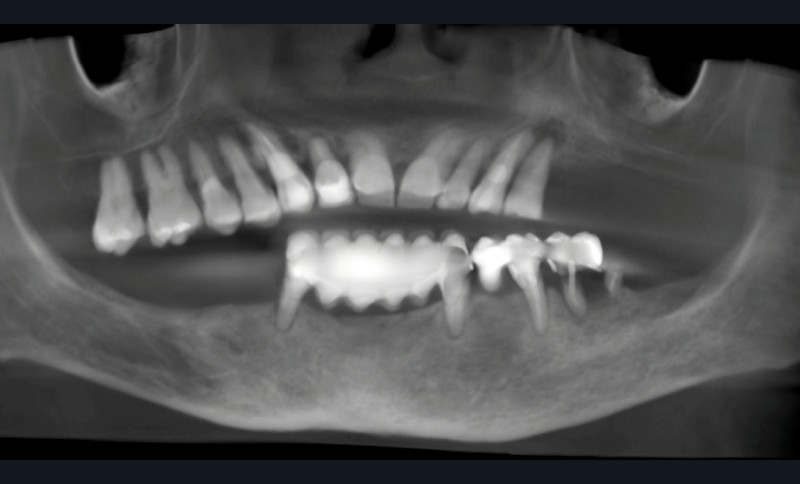

- cone beam pour l’analyse du volume osseux, l’étude des structures anatomiques et la planification implantaire tridimensionnelle (fig. 2) ;